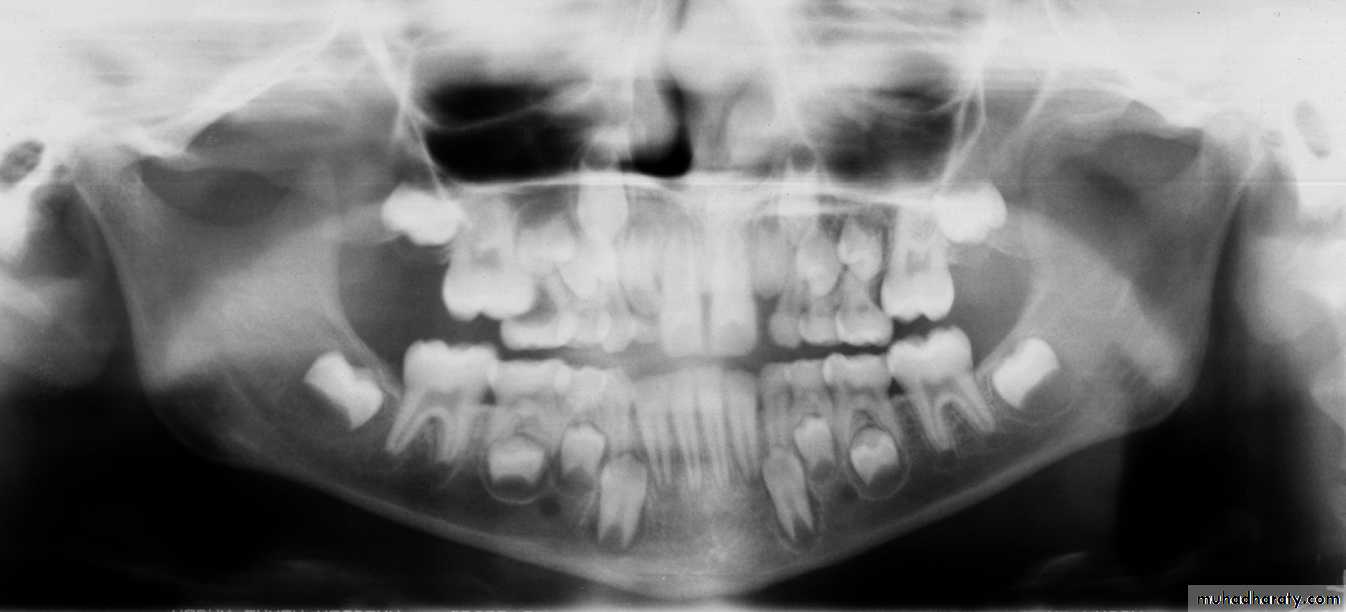

3. ECTOPIC ERUPTION

Ectopic eruption of the maxillary permanent molars

Ectopic eruption

Maxillary left lateralMaxillary left central